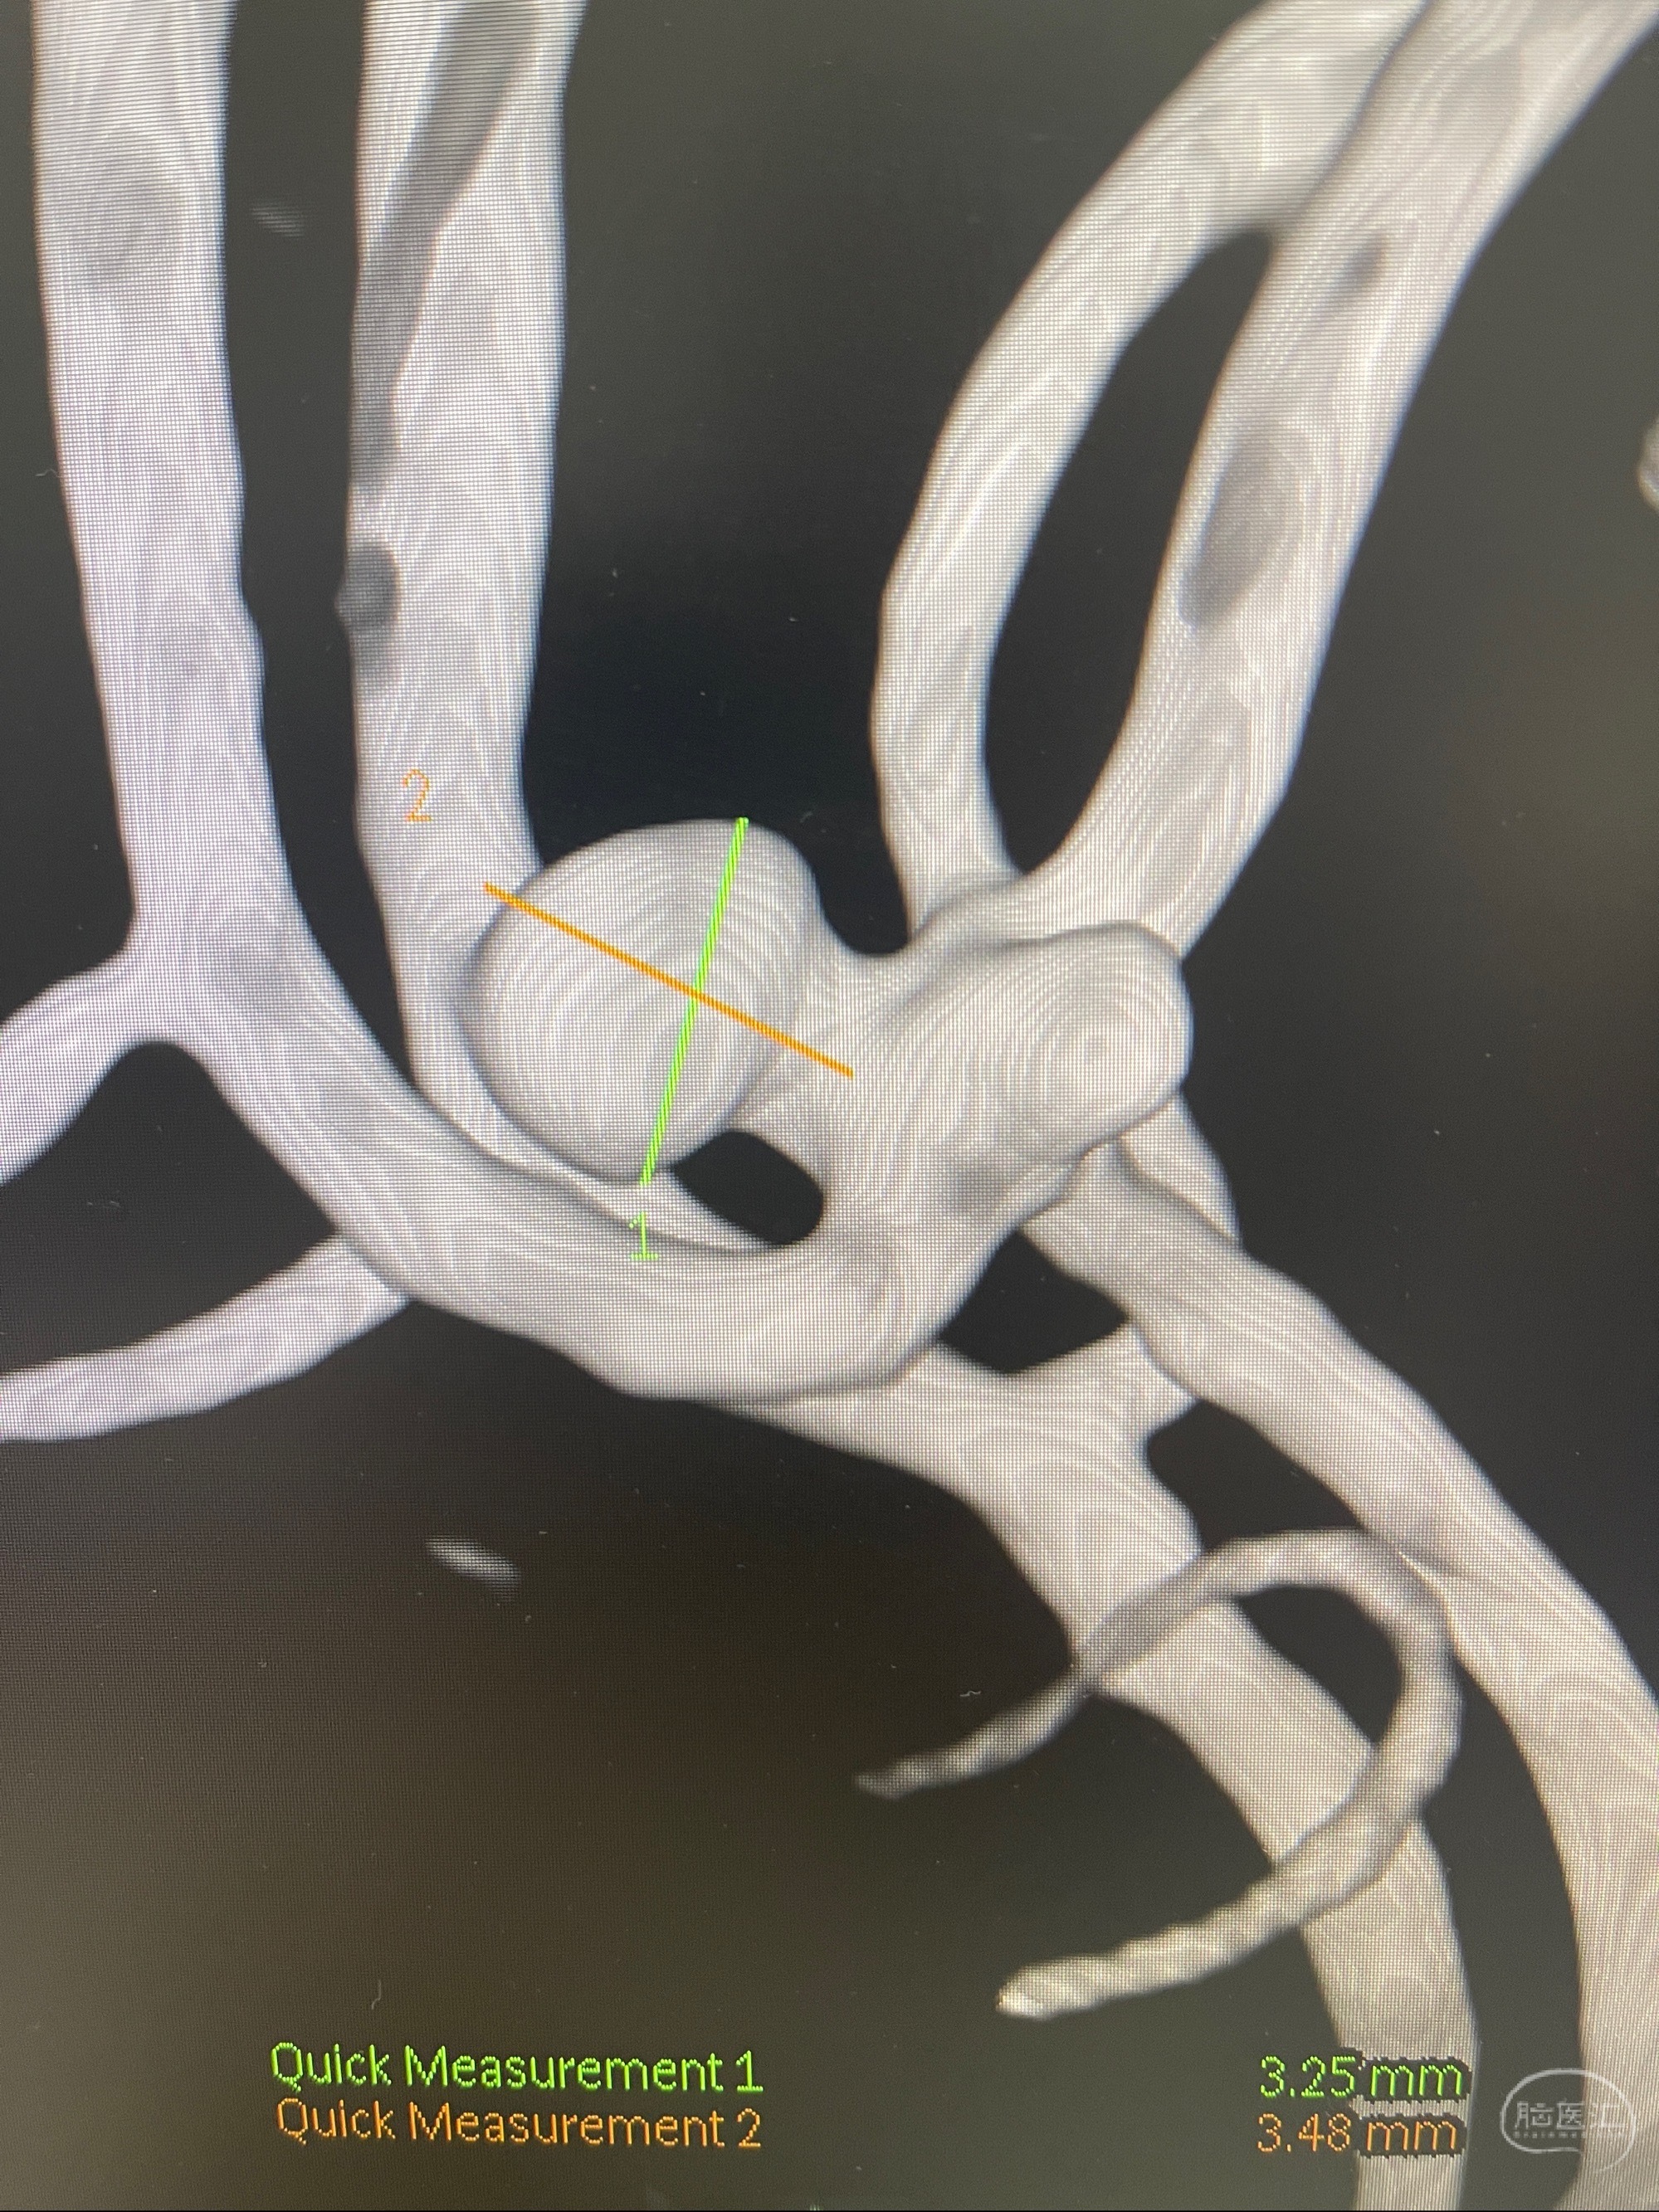

检查;2023-7-18 抚州市第一人民医院 头颈部CTA:左侧大脑前动脉A2段动脉瘤,左侧颈内动脉C4段轻度狭窄,右侧颈内动脉C6段中度狭窄

1.左侧大脑前动脉远侧段(A2-A5)动脉瘤

2023-08-23DSA:左侧前交通动脉瘤,左侧A3/4交界处多发动脉瘤